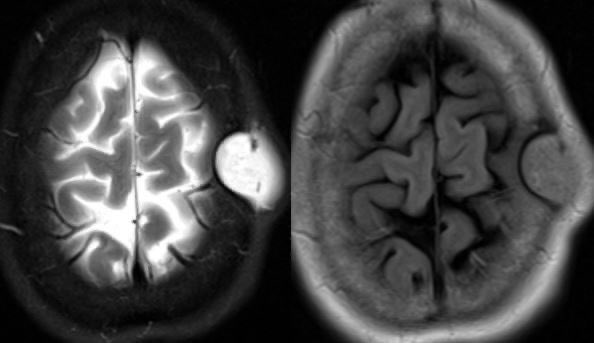

3️⃣Oligodendroglioma

▶️Cortically based mass mainly in ADULTS

▶️Location: FRONTAL and temporal lobes most common

Imaging:

▶️Classically presents as a gyriform cortical/subcortical based mass with GYRIFORM OR CLUMPED CALCIFICATIONS

▶️Consider this diagnosis in an ADULT WITH A CALCIFIED FRONTAL MASS ImageImageImageImage